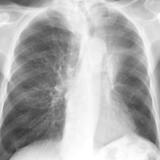

Gallery Lobar Collapse

Lobar Collapse